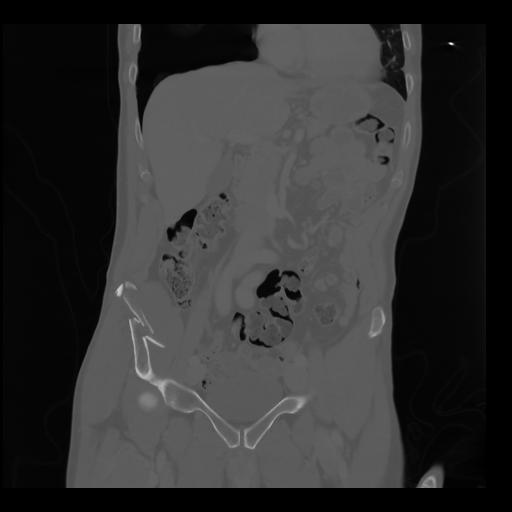

35 CUERPO,CE,Coronal,3.000,CUERPO,Coronal,